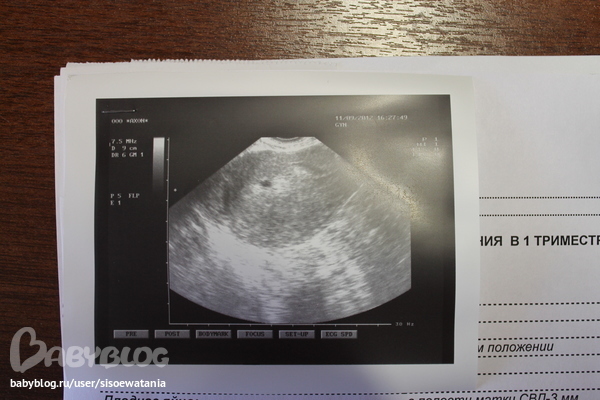

СХОДИЛА Я НА УЗИ ТОЛКО ЧТО, И ВОТ, ДАЖЕ ФОТОЧКА ЕСТЬ

ПЛОДНОЕ ЯЙЦО 3 ММ, 4-5 НЕДЕЛЕК НАМ.